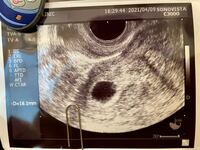

胎嚢は1日1mm大きくなると言われていますが、 +4mm しか成長していません。 そして、胎芽(赤ちゃん)や卵黄嚢も見えていませんでした。 この胎芽期を経て、骨の形成が始まり、成長に必要な器官が成熟してくる時期が胎児期と呼ばれます。 正常な妊娠であれば、胎嚢(たいのう)と呼ばれる赤ちゃんの袋が確認できたあと、卵黄嚢(らんおうのう)、胎芽、そして胎芽の心拍を確認できるようになります。 胎嚢が確認できても、胎芽と心拍が確認できなければ正常妊娠の確定診断はできません。 妊婦卵黄嚢確認 ブログ記事 1 喜びと不安が交互にくるようなこの1週間。色々な方の経過を見てるとこの位の時期からつわりが始まっている人が多い気がして特につわりらしい症状がないとそれはそれで不安になります今までは判定で陽性を貰う事が目標に

低hCGからの胎嚢確認 サクラ咲ク〜不妊治療とその未来〜 21年05月05日 1755 年12月ET5w1d判定日から10日後。 初めての胎嚢確認の日がやってきました。 この日はオットも同行胎嚢確認の日の診察は判定日にhCGが十分出ていたら血液検査なしで即内診のようですが、私は判定日のhCGが328と低かったので血液検査アリこの日の待ち時間は長く1時間を少しオーバーした卵黄嚢のみ確認 心拍確認できないのがちょっとねぇ。でも先週から比べると成長しているので、また一週間後みてみましょうね。 と先生に言われました。7w5d 胎嚢215mm 卵黄嚢、胎芽確認、心拍確認できず エコーが入ると、 卵黄嚢 ; 卵黄嚢(YS)と胎児心拍(FHR)の確認 卵黄嚢(YS)は、受精後23日目(妊娠5週2日目)までに 100%胎嚢の中に出現するそうです。 エコーで見ると、リングのように輪っかになっているのがわかるようです。 しかし、その大きさが46mm以上ある場合は、

この日はオットも同行 胎嚢確認の日の診察は 判定日にhCGが十分出ていたら 血液検査なしで即内診のようですが、 私は判定日のhCGが 328 と低かったので 血液検査アリ この日の待ち時間は長く 1時間を少しオーバーした頃 5F内診室前に呼び出し。 BT22(5w6d)の診察までは出血もなく落ち着いて過ごせました。 診察ではエコーでのチェックです。以下エコー写真でます。 5w6d,エコー GS(胎嚢) 106㎜ やっぱり小さい?心配で調べまくりましたが、やはりどのサイトにのっている大きさよりも小さい。先生も少し小さ目かなみたいなことは言って